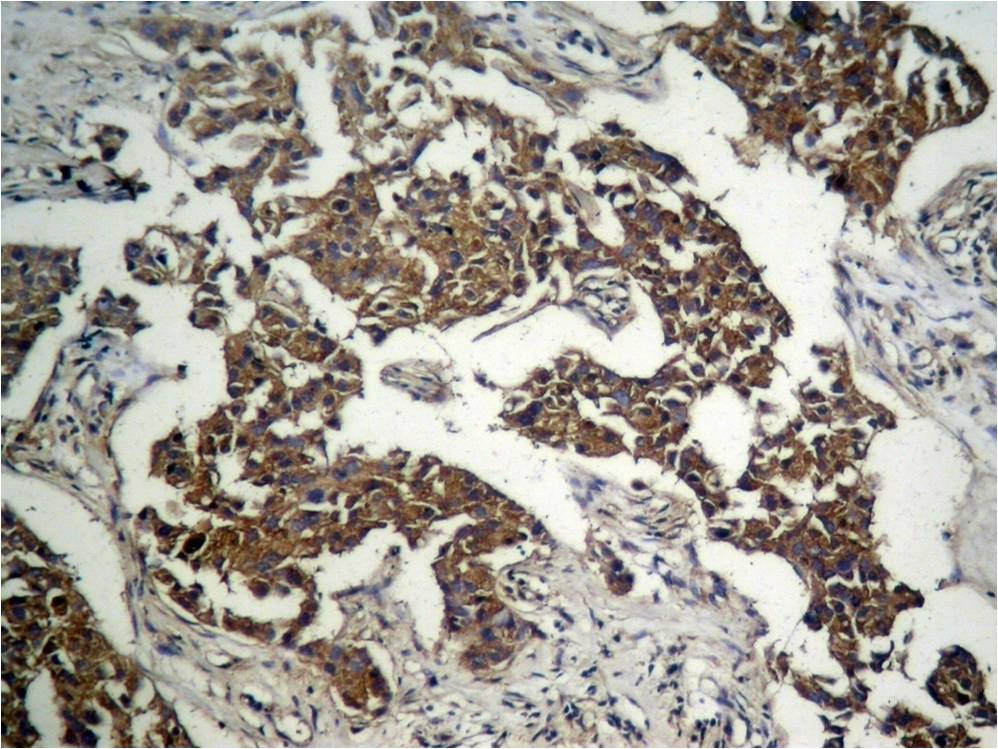

Immunohistochemical analysis of paraffin-embedded human breast carcinoma tissue using GSK3β (Phospho-Ser9) Antibody #11002 (left) or the same antibody preincubated with blocking peptide (right).

Immunohistochemical analysis of paraffin-embedded human Lung carcinoma tissue using GSK3β (Phospho-Ser9) Antibody #11002.